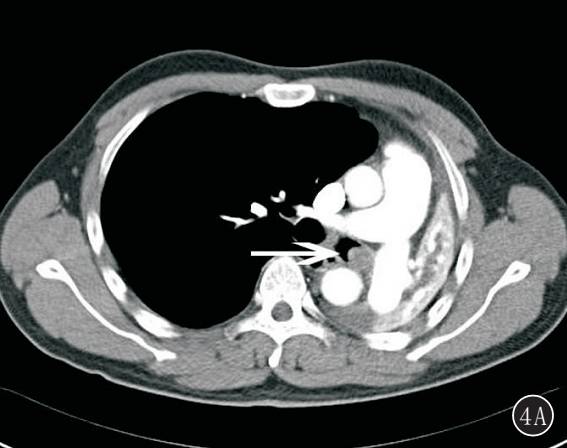

图 4A,B 左肺未分化多形性肉瘤(中央型)。 A. 左主支气管腔内可见软组织肿块影,左肺完全不张;B. 肿瘤由大量异型明显梭形细胞组成,核大深染(HE ×100)